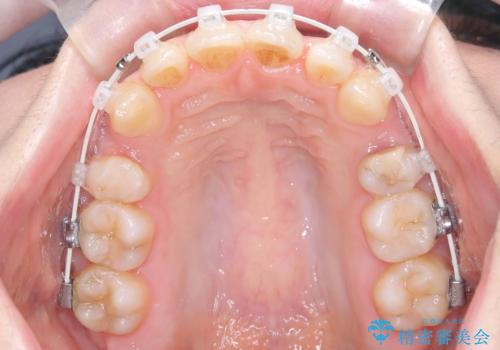

- 矯正装置

- ワイヤー(審美装置)

- 治療期間

- 2年6ヶ月